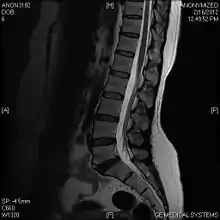

Limbus vertebra

A limbus vertebra is a bone tubercle formed by bone trauma on a vertebral body, bearing a radiographic similarity to a vertebral fracture. The anterior-superior corner of a single vertebra is the common site for this defect although it can also be seen at the inferior corner as well as the posterior or anterior margin. Anatomically, it is assumed to be an intra-vertebral body herniation of the disc material occurring during adolescent growth spurt when the ring apophysis has not yet fused. It was first described by Schmorl in 1927 and later in detail by Leif Sward and Adad baranto.

Viewed in a lateral radiograph, it appears as a triangular shaped bone fragment, not unlike an anterior lip fracture, but with softer edges.

Limbus vertebra is not always symptomatic, but severe cases may lead to more serious pathological conditions and chronic pain. In rare instances, a posterior limbus vertebra has been described causing radiculopathy due to nerve root compression.